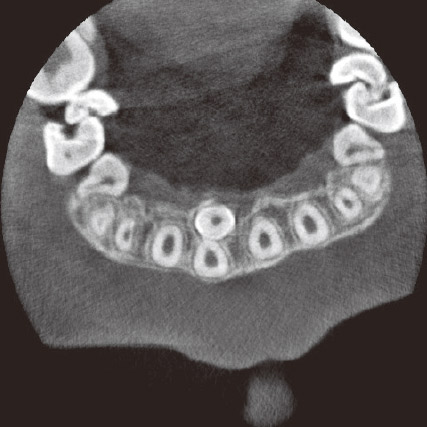

本症例のCBCT所見では逆性埋伏であったが1口蓋側の浅い位置に確認できた(図5a、b)。CBCTで過剰歯と永久歯との位置関係を正確に把握できるため逆性でも1口蓋側粘膜弁をわずかに形成するのみで骨削除することなく抜歯することができた(図6a)。ボリュームレンダリングは患者や家族にも埋伏歯の状態や手術手技を理解しやすく、術者にとっても手術前後のイメージトレーニングには最適である(図6b)。ただし、診断のツールとしては参考程度にするべきである。その理由としてボリュームレンダリングは角度によってイメージが大きく異なり構築するレベルによって画像が変化するためで、スライス画像による最終診断が必要である。これにより術者は低出血・低侵襲で安心・安全な治療を行うことができる。

図5a 初診時CBCT矢状断像。3DXはエナメル質も鮮明に判別できるため周囲骨の状態を確認できる。 -

図5b 初診時CBCT水平断像。切歯管や永久歯、鼻腔底との位置関係が容易に把握できる。 -

図6a 上:術中写真 CBCT所見とほぼ同じでピンポイントで過剰歯にアプローチできる。図6b 下:初診時ボリュームレンダリング。患者への過剰歯の位置関係の説明・理解に有効である。